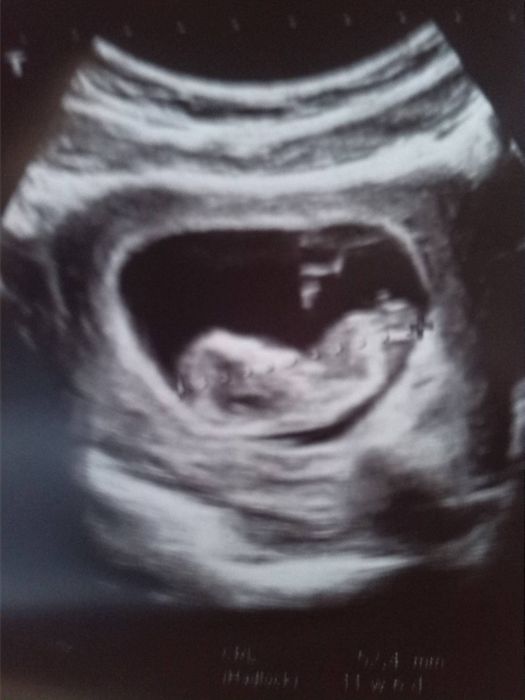

ahojky Smile uz mam po screeningu,mrnousek je v poradku,jen jsme o par dni napred mela bych byt 11+4 a jsem 12+2 a mame 57,1mm,TP se nam presouva na 24.1. , konecne jsem se dostala na pocitac tak vam posilam nejake fotky ..omlouvam se za kvalitu je to prefoceny do telefonu a mrnousek delal porad kotrmelce,doktorka se ho snazila zastavit,tak ji ukazel prdelku a po delsi trpelivosti pani doktorky se nechal zmerit,ale stejne se zakryva rucickama :D